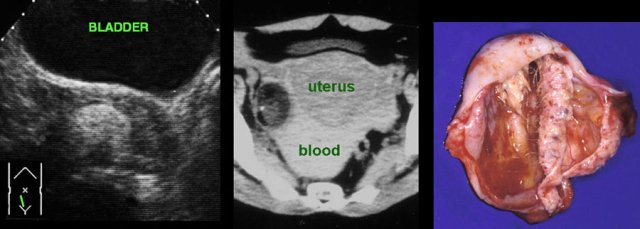

TOA case 3

Large

left sided TOA with air-configurations.

This is a rare finding in TOA, successful

treatment with only antibiotics.

TOA case 4 (infected endometriotic cysts)

These images are of a 29-year old woman, suspected for appendicitis. CRP 185, WBC 17.

US shows a normal compressible appendix, thereby excluding appendicitis.

Large, thick-walled, septated cystic structures, filled with debris-like material, were found on both sides of the uterus (ut.), touching each other posteriorly (“kissing ovaries”).

This is somewhat suspect for bilateral infected endometrotic cysts.

The patient was treated with antibiotics and laparoscopic drainage.

There was a protracted course, but eventually regression of the abnormalities.

An MRI six months later, demonstrated all the signs of deep infiltrating endometriosis, also invading the rectum, thereby confirming the diagnosis of endometriosis.